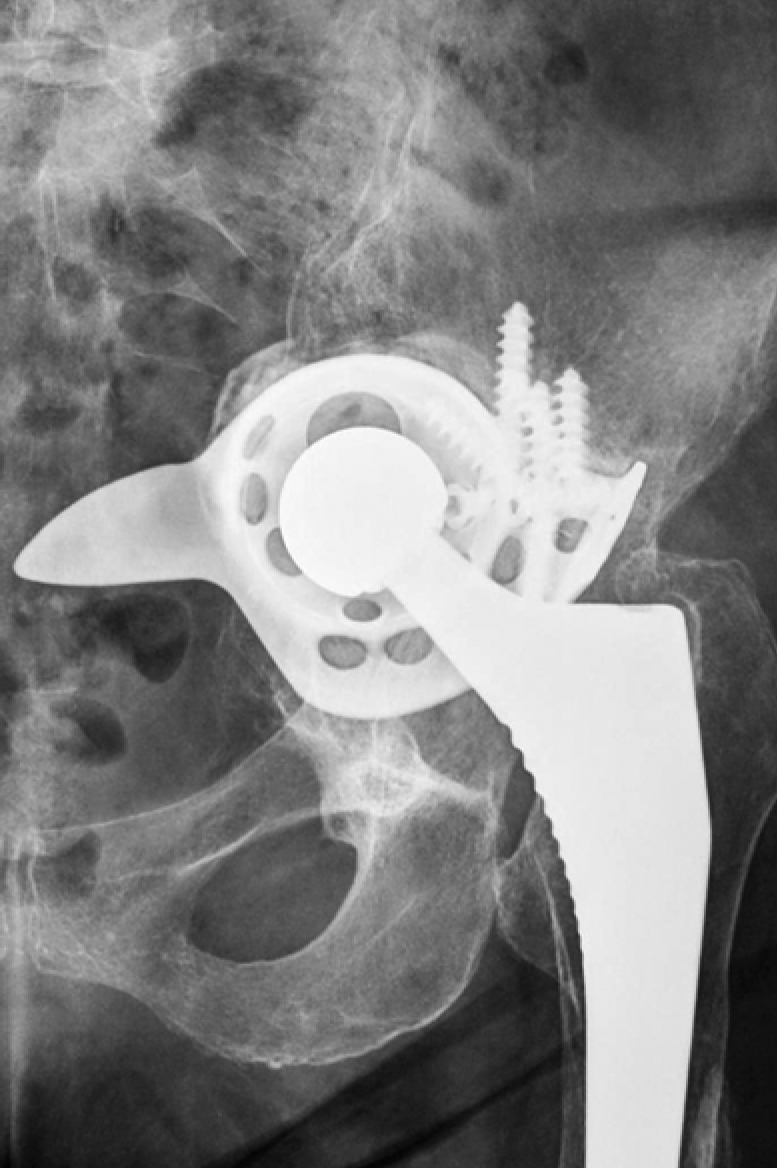

Lytic defects and complete defects of the anterior column, despite their extent, require the restoration of the sphericity of the acetabular region, which can be reconstructed using bone grafts, augments, and standard hemispherical components (Figure 2 a, b).

Figure 2. Various options for acetabular reconstruction in Paprosky type 3B defect: a — lytic acetabular defect reconstructed using impaction bone grafting with implantation of a standard cemented acetabular component; b — complete anterior column defect reconstructed with an augment and a hemispherical acetabular component; c — complete medial wall defect reconstructed with augmentation and combined implantation of a hemicap cage; d — combination of complete medial wall and anterior column defects reconstructed with a Burch-Schneider antiprotrusio cage and a cemented acetabular component; e — combination of complete medial wall and posterior column defects reconstructed with a patient-specific acetabular component

Reconstruction of complete medial wall defects, as well as combined complete defects of the medial wall and anterior column, requires the use of antiprotrusio devices to ensure the stability of the acetabular component. For this combination of defects, a wide range of types and sizes of standard cages may be necessary (Figure 2 c, d). In cases of combined complete defects of the medial wall and posterior column — the most challenging in terms of biomechanical stability of the acetabular component — there is a need for a highly reliable primary fixation of the implant, which cannot always be achieved with standard revision systems (Figure 2 e).